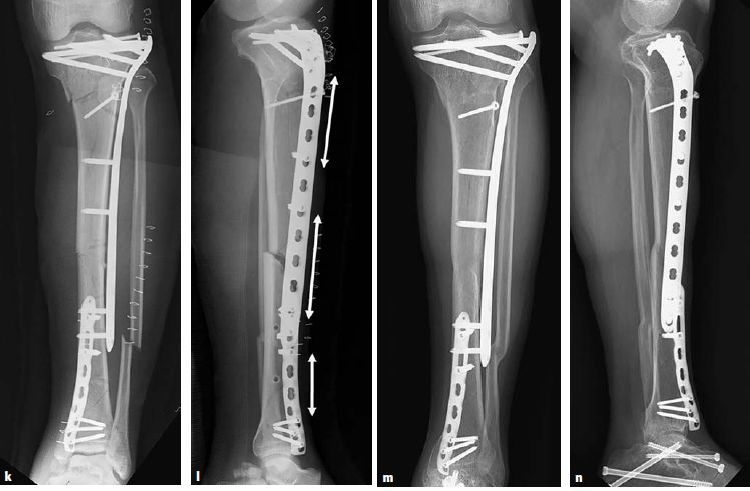

图6.8.1-17 a-n 一名62岁的男性车祸后左腿受伤(41A3.3)

a-b  X线显示左侧胫骨的节段性骨折。骨折近端有多条骨折线和一个楔形骨块,但是它们都没有移位或移位程度很小。整个骨折可以通过一根髓内钉进行固定,但是由于骨折位置非常高位,因此髓内钉手术将非常具有挑战性,因此最终选择采用MIPO技术进行钢板固定

c-d  关节面的骨折通过软骨下螺钉进行稳定固定,使用点式复位钳通过微创技术经皮复位近端的干骺端骨块,滑入胫骨近端锁定加压钢板,而后使用两枚克氏针在钢板两头进行临时固定

图6.8.1-17 a-n(接上图) 一名62岁的男性车祸后左腿受伤(41A3.3)

e-f  通过一枚单皮质复位螺钉将中间节段拉向钢板

g-h  在骨折区的内侧进行手法加压使得干部复位

i-j  当钻透坚硬的皮质时,干部会被推开,而后再次通过一枚单皮质复位螺钉将其复位

k-n  关节面的骨折通过软骨下螺钉进行稳定固定,使用点式复位钳通过微创技术经皮复位近端的干骺端骨块,滑入胫骨近端锁定加压钢板,而后使用两枚克氏针在钢板两头进行临时固定。

术后X线的力线可以接受。注意骨折的每个部分,工作长度都长达3个螺孔(双头箭头)。拉力螺钉打入近端骨折区来维持楔形骨块。但是一般来说,并不推荐在桥接区域放置拉力螺钉,因为它可能会妨碍跨骨折区的微动,从而妨碍骨折愈合。远端内侧的钢板位置稍微偏前以避免和外侧锁定板的螺钉钉道发生冲突。所有的骨折最终均平稳愈合